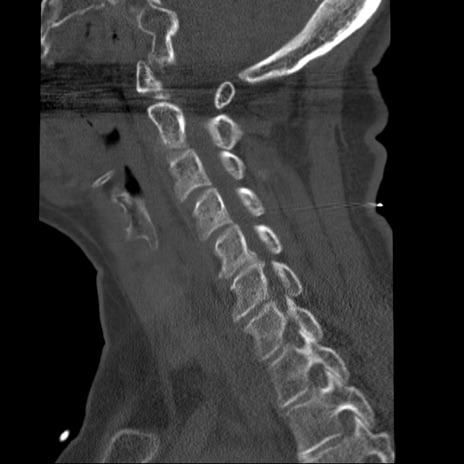

症例50 頚椎CT(矢状断像)

【症例】60歳代女性

【主訴】後頭部〜右後頸部にかけての痛み

【現病歴】本日飲食店でコーヒーを飲んでいたところ、突然後頭部〜右後頸部にかけて痛みが出現し、右上肢の感覚障害を伴ったため救急要請。

【身体所見】脳神経学的に明らかな異常所見を認めず。右上肢に軽度の感覚障害あり。

頚椎CT